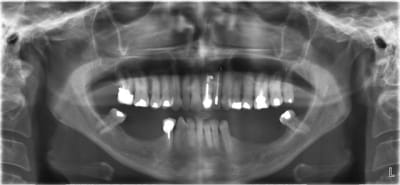

pano_origine_nwhu2w.jpg